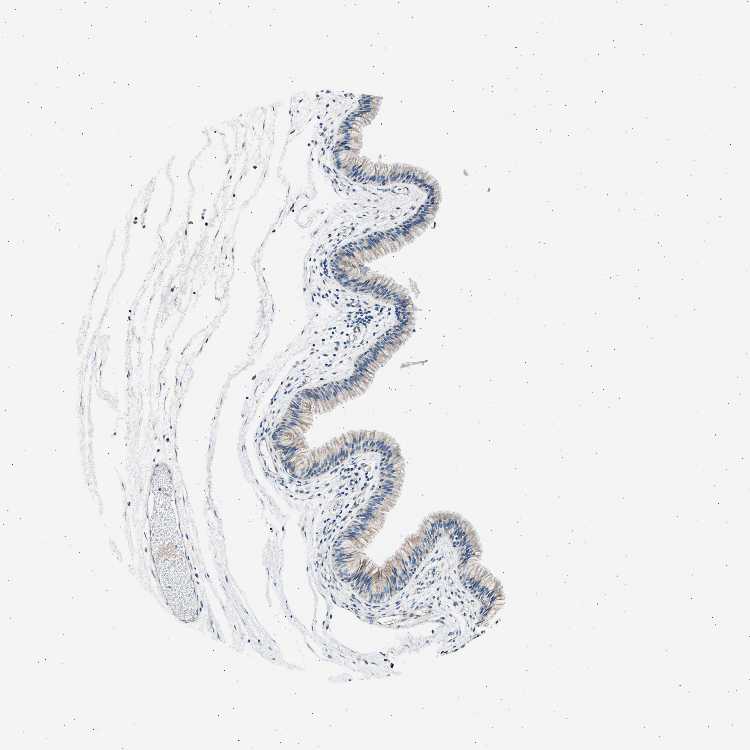

TISSUE PRIMARY DATA NASOPHARYNX Show tissue menu

NASOPHARYNX - Antibody stainingi

Antibody staining in the annotated cell types in the current human tissue is reported as not detected, low, medium, or high, based on conventional immunohistochemistry profiling in selected tissues. This score is based on the combination of the staining intensity and fraction of stained cells.

Each image is clickable and will lead to virtual microscopy that enables deeper exploration of all samples and also displays staining intensity scores, fraction scores and subcellular localization as well as patient and tissue information for each sample.

Antibody HPA015135

Respiratory epithelial cells Low